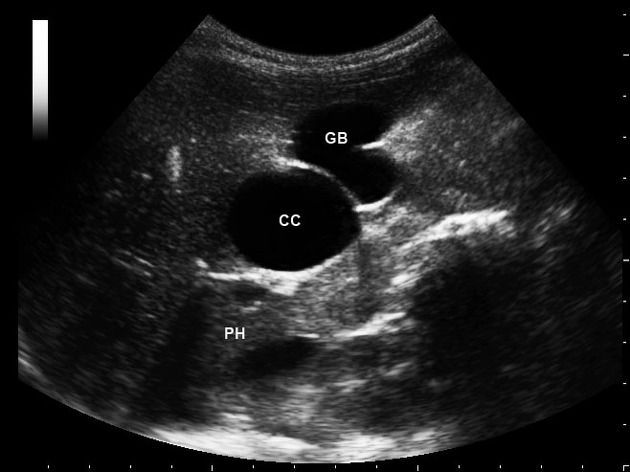

Choledochal cysts refer to cystic dilatations of the biliary tree involving either the intra-hepatic or extra-hepatic ducts, or both. They are more common in women than men. Clinical features include epigastric pain, fever, jaundice, and RUQ mass. Cholangiocarcinoma is one of the most feared complications of choledochal cysts. Other complications include recurrent cholangitis/pancreatitis, liver abscess, biliary obstruction, portal hypertension, and cirrhosis. Ultrasound is the best non-invasive test for the diagnosis. However, a definitive diagnosis is made by ERCP. Treatment includes complete resection of the cyst with a biliary-enteric anastomosis to restore continuity of the biliary system with bowels.